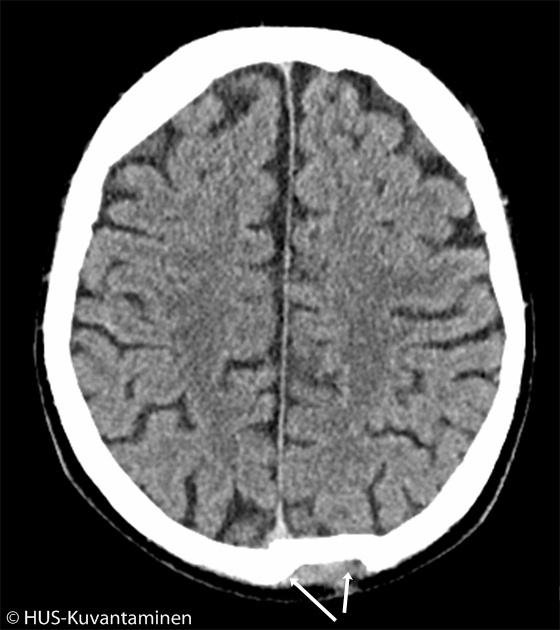

Kallonmurtuma pään TT-kuvassa (kuva 2 löydösmerkinnöin).

Kallonmurtuma pään TT-kuvassa (kuva 4 löydösmerkinnöin).

Lisäksi okkipitaalisesti on nähtävissä laaja, pirstaleinen murtuma (nuolet), joka halkaisee vasemmanpuoleisen foramen jugulariksen ja jatkuu temporaaliluuhun asti. Oikeanpuolinen ehjä foramen jugulariksen aukko on ympyröity, vasemmalla murtumalinja seuraa sen kulkua.